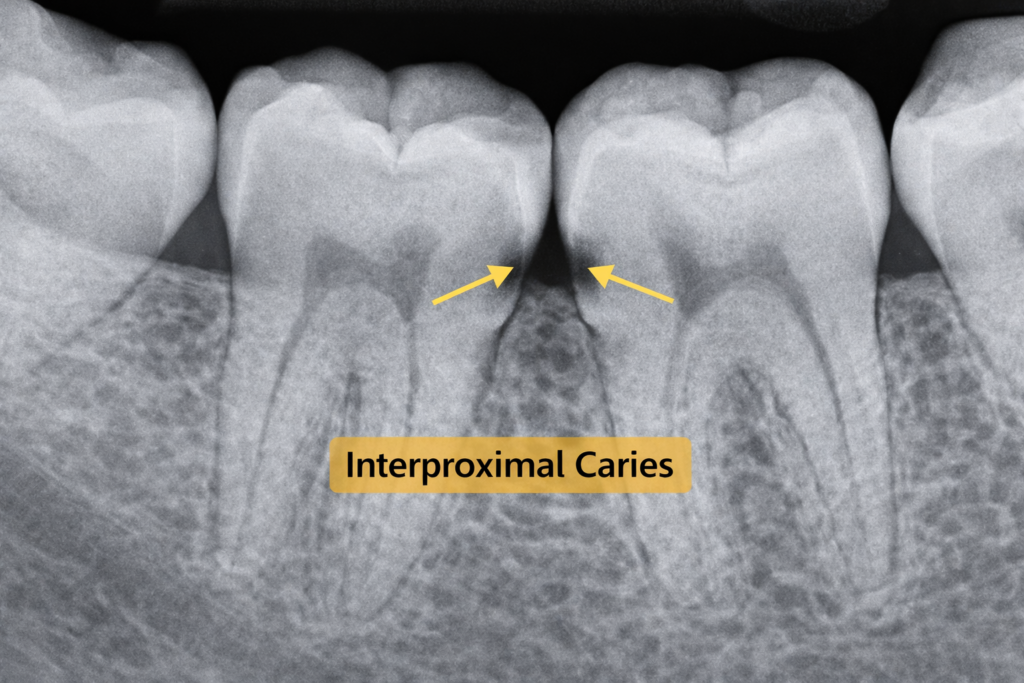

6) تسوس السطح الأملس وبين الأسنان

هذا النوع يظهر على الجوانب الملساء للأسنان، وكثيراً ما يبدأ بين سنين متجاورين. المشكلة هنا أن المريض قد لا يراه مبكراً بالعين المجردة، خاصة إذا كان هناك تزاحم يستدعي تركيب تقويم أسنان ثابت لتعديلها. لذلك قد يكون الفحص الدوري أو الأشعة هو الطريقة الأفضل لاكتشافه قبل أن يصبح حفرة واضحة.

تشخيص تسوس الأسنان لا يعتمد على النظر فقط. عادة يبدأ الطبيب بالسؤال عن الألم أو الحساسية، ثم يفحص الأسنان بصرياً، وقد يستخدم أدوات لفحص المناطق اللينة أو المتأثرة. بعد ذلك قد يطلب أشعة سينية لإظهار التسوسات غير المرئية بوضوح، خاصة تلك الموجودة بين الأسنان أو في العمق، لتحديد ما إذا كان السن يحتاج إلى تركيبات لتعويضه.

هذا مهم جداً في المقالات التي تحمل نية بحث مثل أنواع تسوس الاسنان بالصور، لأن الصورة قد تساعد على التوعية، لكنها لا تكشف دائماً عمق التسوس أو قربه من العصب. لذلك يظل الفحص السريري والأشعة هما الأساس لتحديد المرحلة بدقة ووضع خطة العلاج.

ليس دائماً. بعض الحالات، خاصة تسوس بين الأسنان أو التسوس العميق، قد لا يظهر بوضوح من الخارج، ولهذا تستخدم الأشعة السينية للمساعدة في اكتشافه وتحديد عمقه.